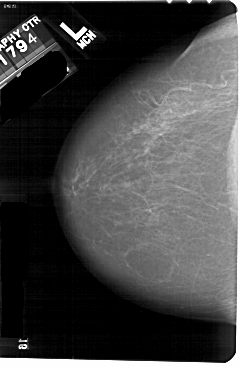

A_1175_1.LEFT_MLO

LEFT_CC LINES 5491 PIXELS_PER_LINE 3601 BITS_PER_PIXEL 12 RESOLUTION 43.5 NON_OVERLAY

LEFT_MLO LINES 5491 PIXELS_PER_LINE 3661 BITS_PER_PIXEL 12 RESOLUTION 43.5 NON_OVERLAY